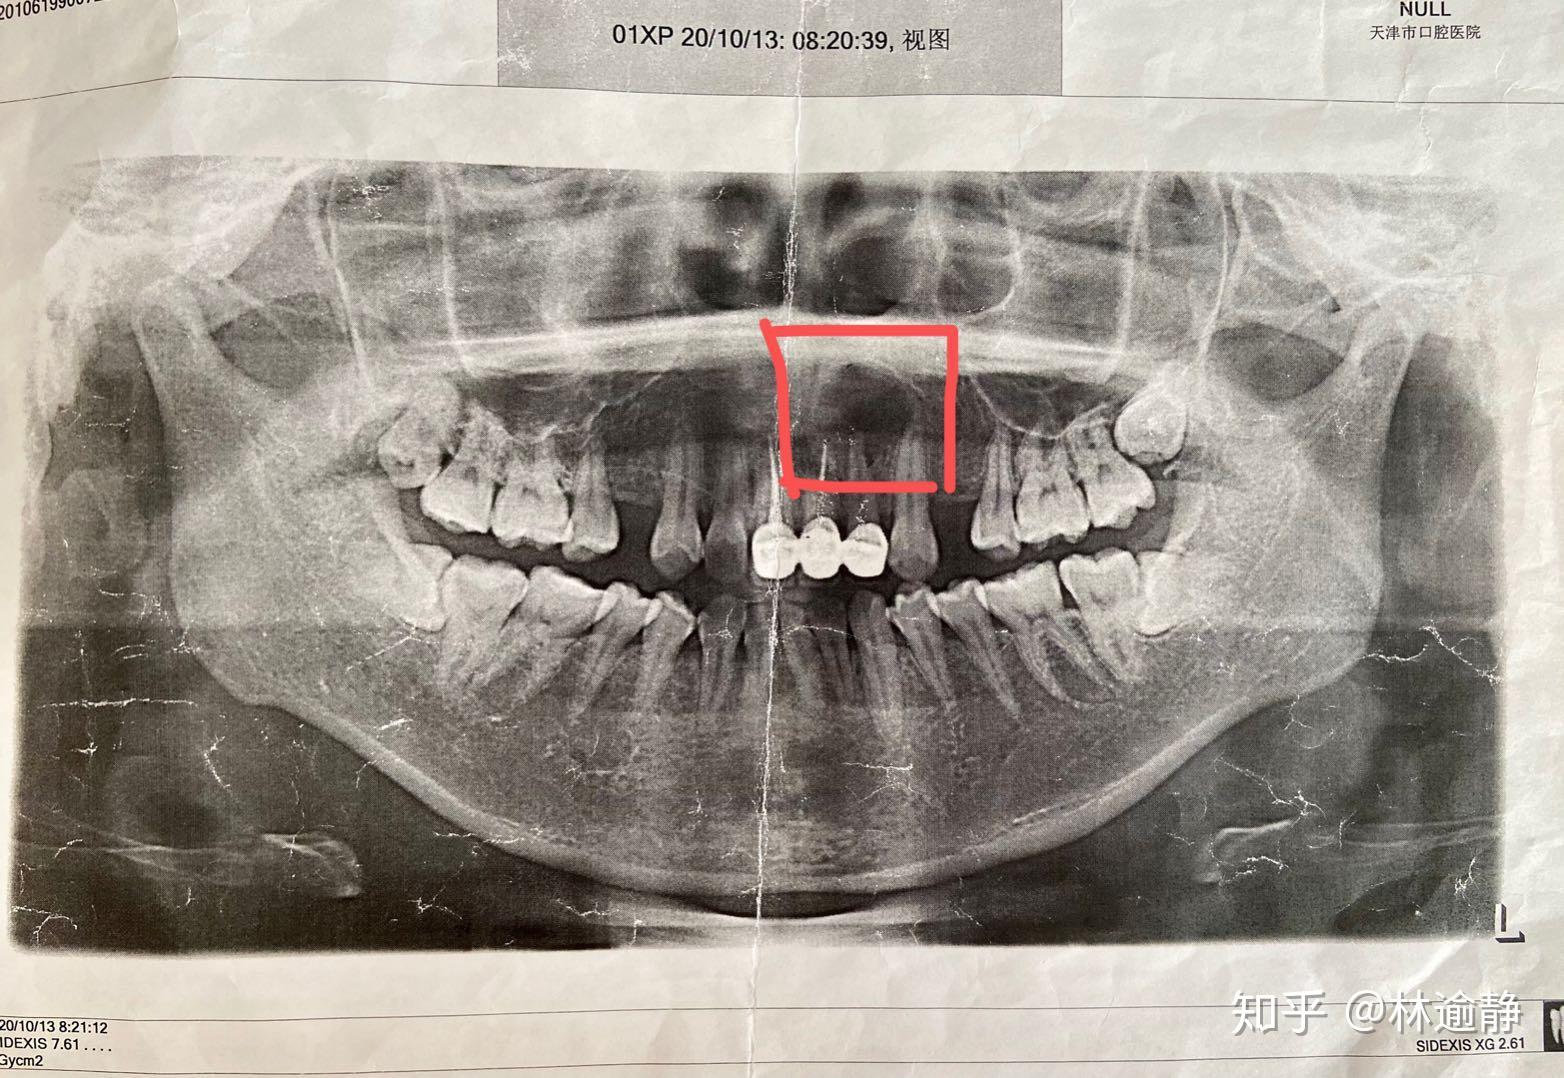

记录帖医生说是下颌根尖囊肿最近准备入院做手术了